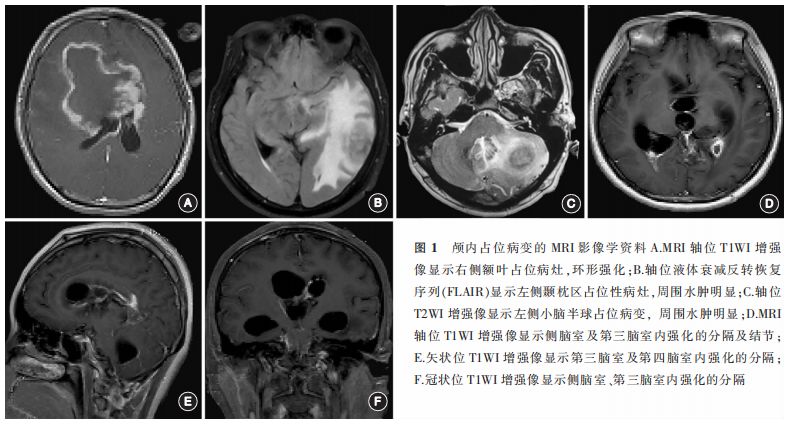

在23例新型隐球菌感染致高颅压患者中,头颅MRI和(或)CT明确脑积水,疑似不完全梗阻性脑积水者5例,脑室大小正常甚至体积减小者18例。17例颅内占位病变的患者影像学表现无特异性,与其他炎性反应及肿瘤难以区分,位于脑实质内的表现为T1WI呈等或低信号,T2WI呈高或等信号,病灶一般呈环形强化,周围脑组织水肿明显(图1 A~C);脑室内多发囊性占位者可见强化的分隔及脑室扩大、室旁水肿(图1 D~E)。

颅内占位病变的17例患者中,2例行立体定向活检术确诊为真菌性占位的患者给予抗真菌治疗后症状明显改善。15例采用开颅占位切除术的患者术后症状改善良好,无神经功能缺失,仅1例因合并脑室内铜绿假单胞菌及脑积水后死亡。3例侧脑室内多发囊性占位者神经内镜下可见脑室壁多发菌斑结构(图2A),位于颅底、脑实质及脑室系统的肉芽肿血供不丰富,周围组织水肿严重(图2 B~D)。所有确诊为真菌感染的病例,炎性反应的实体部分镜下可见明显的孢子、菌丝等真菌典型结构(图3 )。